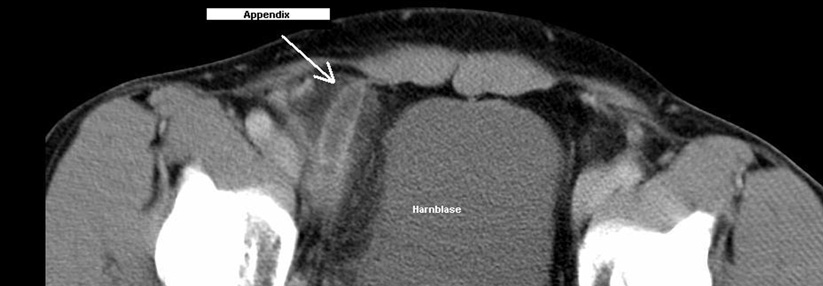

Überdurchschnittlich häufig, so ein Ergebnis der Untersuchung, erfolgte die Fehldiagnose bei Mädchen und Frauen. Auffallend oft waren zudem Patienten mit Begleit­erkrankungen betroffen. Dasselbe galt, wenn sich die Kranken mit der Symptomkombination Bauchschmerz und Verstopfung vorstellten. Alleiniger Bauchschmerz oder Abdominalschmerz plus Übelkeit schienen dagegen eindeutigere Hinweise zu liefern. Wurde bei Erstvorstellung ein CT angefertigt, stiegen die Chancen auf die richtige Diagnose. Wurde das Abdomen lediglich geröntgt, sanken sie. Was wohl damit zu tun hat, dass die Ärzte bei Anordnung der Tomographie schon den ganz konkreten Verdacht hatten, so die Vermutung der Autoren.

Auch die Sonographie gibt oft nicht die entscheidenden Hinweise: 22,3 % der Ultraschalluntersuchung bei Erwachsenen ließen die Appendizitis im ersten Anlauf unentdeckt. Dennoch sei eine CT sicherlich nicht bei allen Verdachtsfällen notwendig, meinen die Autoren. Bei ungeklärtem Bauchschmerz sollte man die Patienten aber einige Zeit im Blick behalten, so sein Rat.